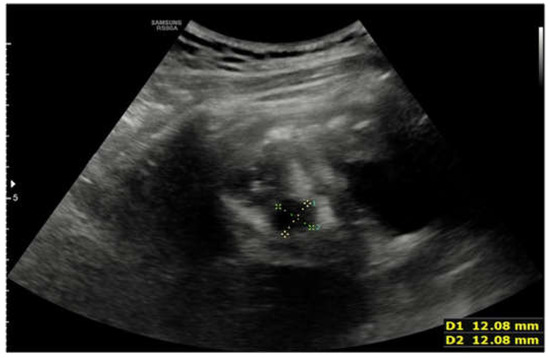

2. Case Report